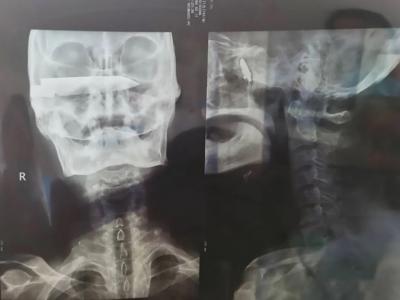

Following a number of CT scans and X-rays, medics reportedly found that the blade was placed at the base of the patient’s skull, lodged against his eye socket and pressing against his optic nerve.